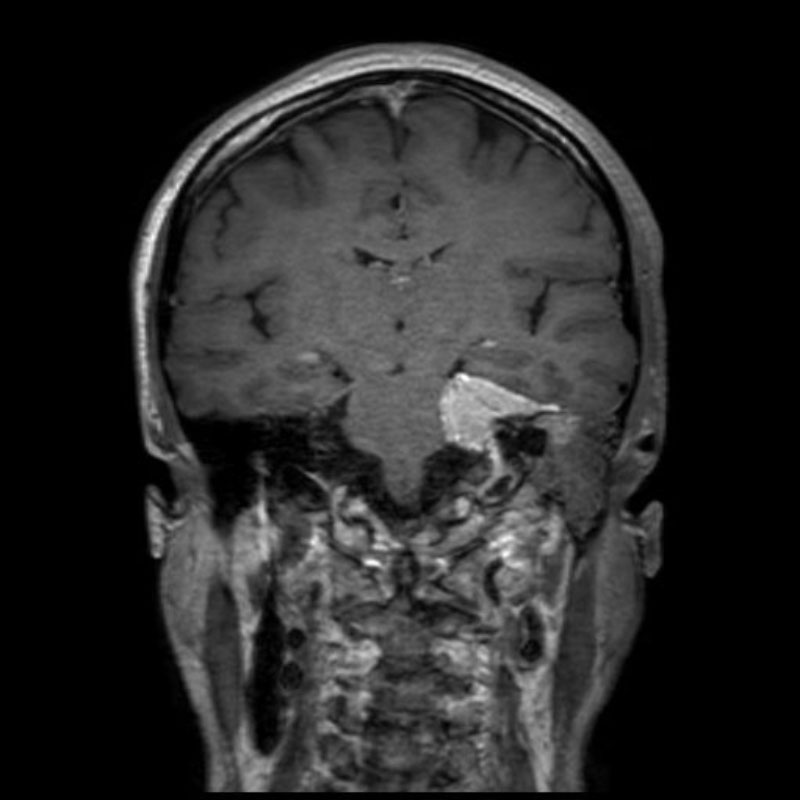

640

'25年6月

80代

傍矢状洞髄膜腫

頭蓋内腫瘍摘出術

No.’25_42 手術前1

No.’25_42 手術前2

No.’25_42 摘出 前

No.’25_42  摘出 中

No.’25_42 摘出 後